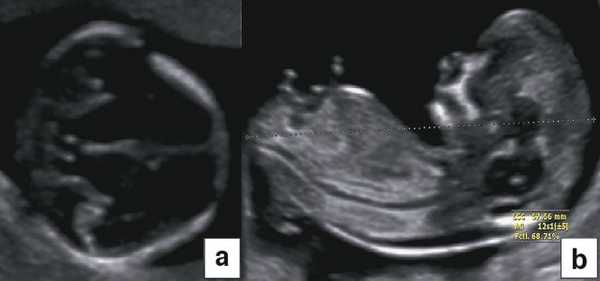

Некоторые ультразвуковые измерения в I триместре обязательны для выполнения. В большинстве случаев гестационный возраст до 15 нед с определенной степенью точности оценивают по показателям бипариетального размера (БПР) и копчико-теменного размера (КТР) (рис. 1). В дальнейшем эту информацию дополнять не будут, а использовать будут в основном для установления задержки внутриутробного развития, при планировании обследования по поводу врожденных аномалий и послеродовых осложнений. УЗИ на сроках между 11 нед 0 дней и 13 нед 6 дней необходимо постоянно сравнивать с данными обследования на сроках между 7 и 10 нед. Таким образом, УЗИ в I триместре должно помочь обнаружить ряд аномалий развития плода, например триплоидию [1].

В начале 90-х годов прошлого века в практику был внедрен метод измерения толщины воротникового пространства (ТВП) в I триместре беременности, и к настоящему времени его считают показателем не только анеуплоидии, но и широкого спектра наследственных синдромов и пороков развития [2]. K. Николаидес (K. Nicolaides) с группой исследователей предложили новую модель скрининга на анеуплоидию и установили правила использования этого метода, в частности необходимость применения кривой обучения, проведения аудита, качественного (процедура оценки качества изображений) и количественного (медиана, дельты-ТВП и т.д.). Фонд медицины плода (Fetal Medicine Foundation) стандартизировал предложенный ими клинический протокол и установил правила сертификации для повышения качества медицинской помощи и уменьшения изменчивости результатов данных скрининга [3, 4]. Измерение ТВП можно проводить вручную (рис. 2a) или полуавтоматически (рис. 2b), чтобы результаты измерений были более воспроизводимыми. Кроме того, компания Samsung разработала дополнительный метод измерения показателей ТВП - 5D NT, позволяющий точно выявить срединно-сагиттальную плоскость и улучшить оценки по шкале Германа (Herman score).

Рис. 4. Диагностика хориальности и количества амнионов в I триместре путем оценки лямбда-признака (a) и T-признака (b).